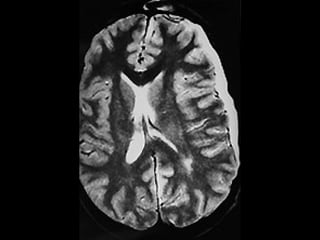

(1) Tumor Quístico del cerebelo con compresión del IV ventrículo con

dilatación del III ventrículo y ventrículos laterales. (2) RM-T2 Tumor

parietal izquierdo y gran edema peritumoral